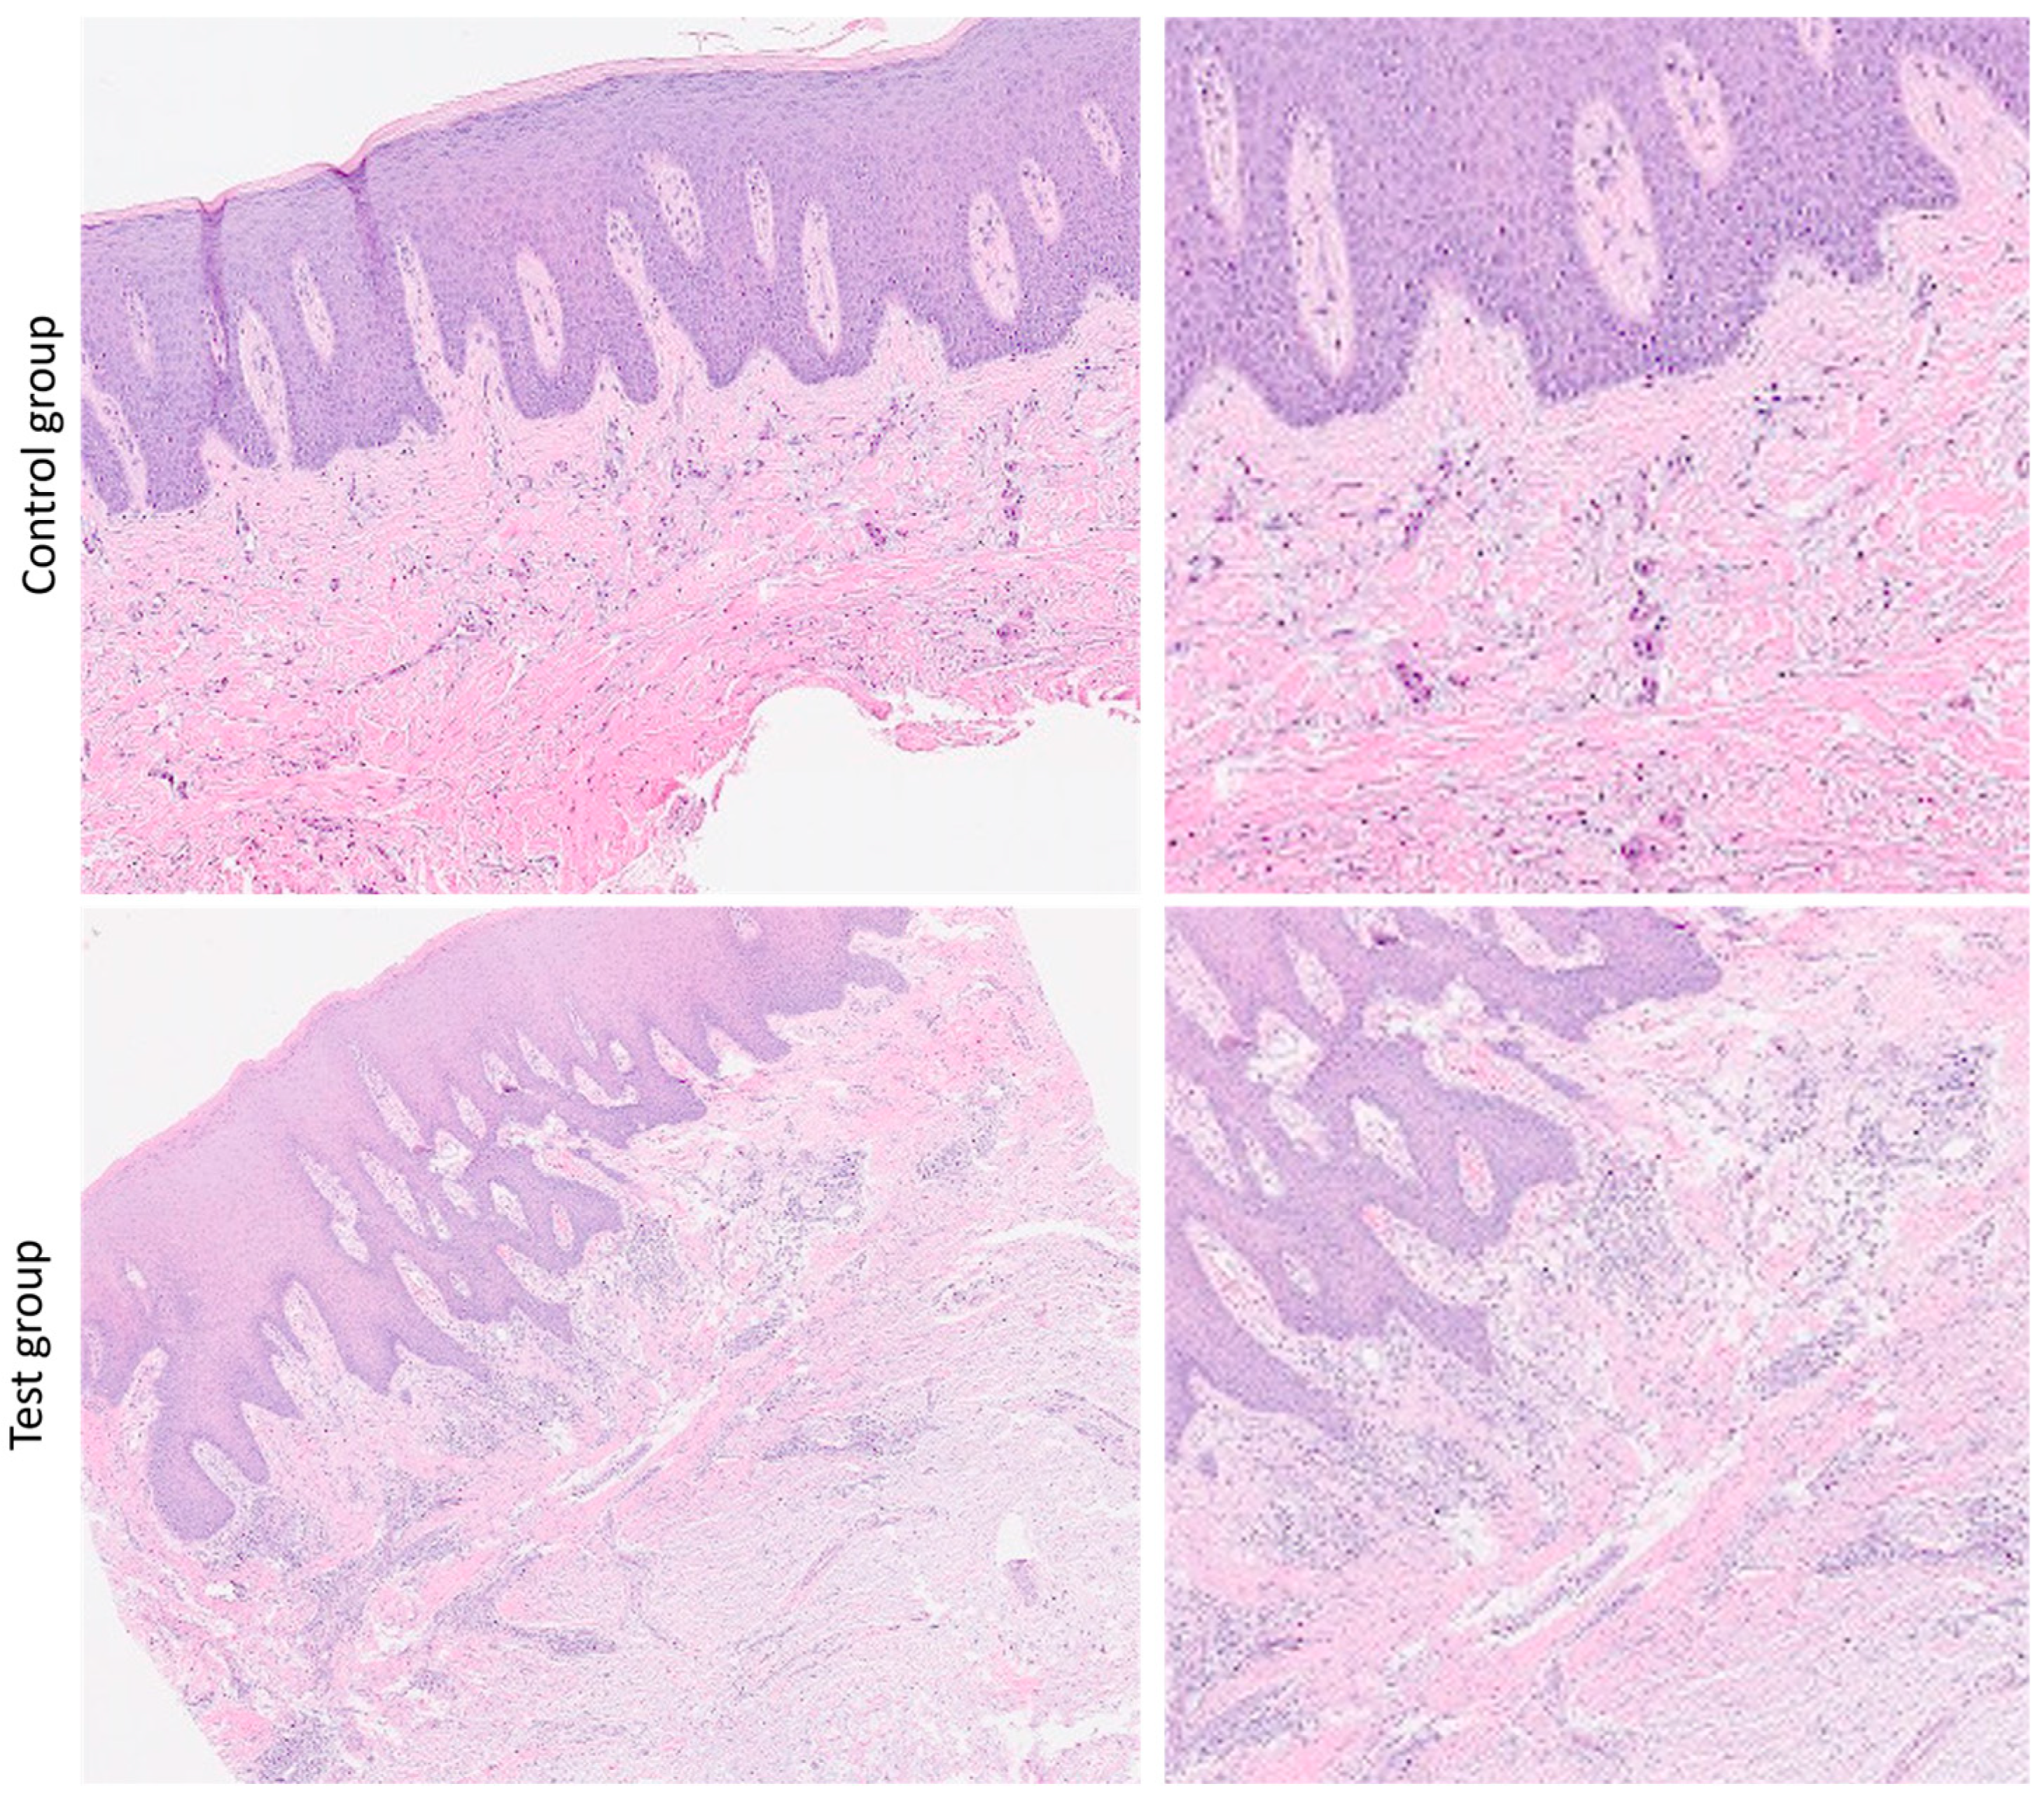

3.1. Histomorphological Analysis

3.3. Immunohistochemical Analysis